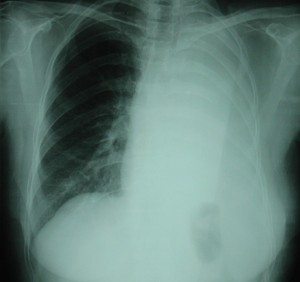

600px-MesotheliomaCTRadyolojik bulgular: Direkt grafide; efüzyon, diffüz plevral kalınlaşma, nodüler yapı görülebilir.

Toraks BT: evreleme ve cerrahi öncesi değerlendirme için gereklidir. Hidropnömotoraks (%73), ilgili hemitoraksda volum kaybı (%73), plevral kalınlaşma (%93), nodüler veya lobüler plevral kitle (%52), kalsifik plevral diafragmatik plaklar veya fibröz plaklar (%62), kosta destruksiyonu (%16), yumuşak doku invazyonu, parankimal fibrozis, kardiyomegali, perikardiyal efüzyon, lenfanjitik yayılım ile uyumlu görünüm, interlober fissür kalınlaşması veya nodüler görünüm (%76), mediastinal genişleme veya düzensiz mediastinal kontur görülebilir.